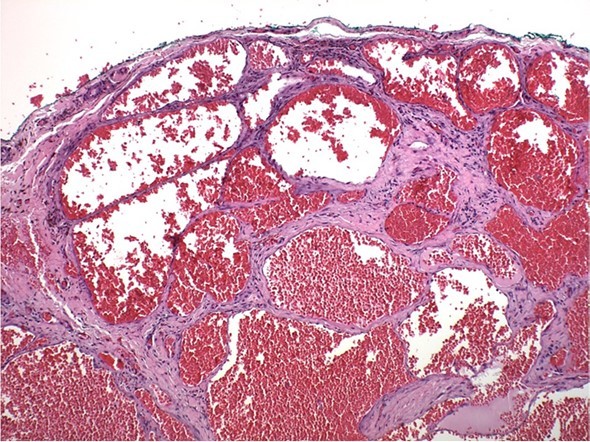

A 73-year old Asian female presented to the office for evaluation of a mass on the left cheek (Figure 1). Medical history reported by the patient included hypertension and osteoporosis. Medications included Losartan 50mg daily and Alendronate 70mg once per week. The patient stated that the mass appeared to be enlarging in size and was noticeable to her family. She denied pain or tenderness in the area of the cheek mass. Oral examination revealed a firm compressible submucosal mass in the left buccal vestibule of the mandible that did not blanche on digital pressure. The mass was negative for any bruit or vascular thrill. The surface mucosa overlying the mass was the same color as the buccal mucosa of the cheek (Figure 2). No imaging studies were indicated, as the mass was localized to the soft tissues of the cheek. The differential diagnosis included dermoid cyst, epidermoid cyst, and mucous retention cyst. The patient was informed of the clinical findings and the plan to remove the lesion as an in-office procedure. Under local anesthesia, using a #15 scalpel a mucosal incision was made and it was immediately observed that the dark purple mass was a suspected hemangioma (Figure 3). With careful blunt dissection, the purple-colored mass was completely excised and sent for histologic analysis (Figure 4). Histopathologic examination revealed a proliferation of irregular dilated capillary sinuses lined by flat endothelial cells. The sinusoidal spaces contained erythrocytes (Figure 5). The diagnosis was consistent with a cavernous hemangioma.

Figure 5.Histopathology of cavernous hemangioma. Note irregular sinusoids lined by endothelium containing erythrocytes. Hematoxylin and eosin, 400x.

In the oral cavity, cavernous hemangiomas are rare painless dark purple-blue colored soft tissue masses that will blanch with digital pressure. Hemangiomas can occur on the gingiva, soft and hard palate of the maxilla, lips, buccal mucosa, salivary glands, and jaw bones.4, 5They can appear as a smooth single or multiple lobulated compressible mass of variable size.1, 6, 7However, hemangiomas can mimic other tumor or cystic lesions as in this case report. In our patient, the surface mucosa was of normal color without the dark purple-blue color that is characteristic of hemangiomas. Histopathology reveals well developed capillary sinuses lined by endothelial cells separated by a connective tissue stroma. The dilated sinuses are often filled with erythrocytes.4, 8